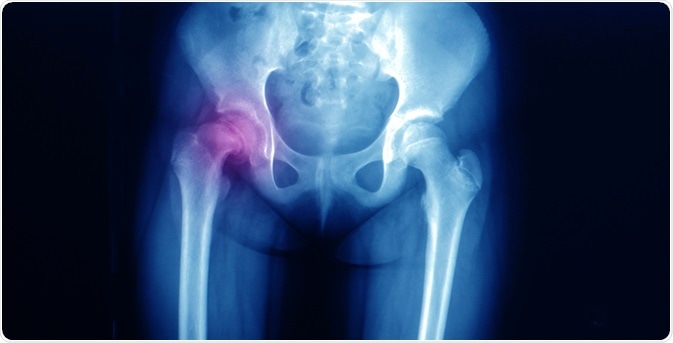

SCFEImage Credit: Yok_onepiece / Shutterstock.com